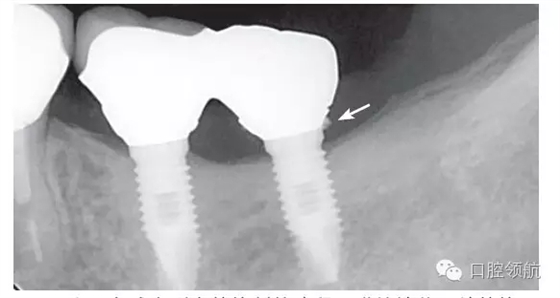

本病例,患者主訴是因?yàn)樯喜啃迯?fù)體脫落,來(lái)院檢查。使用臨時(shí)粘接劑,剩余部分的粘接劑在硬化前,盡量沖洗干凈。但在遠(yuǎn)中范圍,可看到還有剩余的粘接劑,原因是將上部修復(fù)體戴入到制作的個(gè)性化基臺(tái)上,沒(méi)能調(diào)整粘接劑的用量,粘接劑被擠壓進(jìn)入到齦下部位(圖4)。

圖4 為盡力減少剩余粘接劑的殘留,謹(jǐn)慎地戴入并粘接,但在遠(yuǎn)中鄰面,仍可見(jiàn)到殘留的粘接劑。